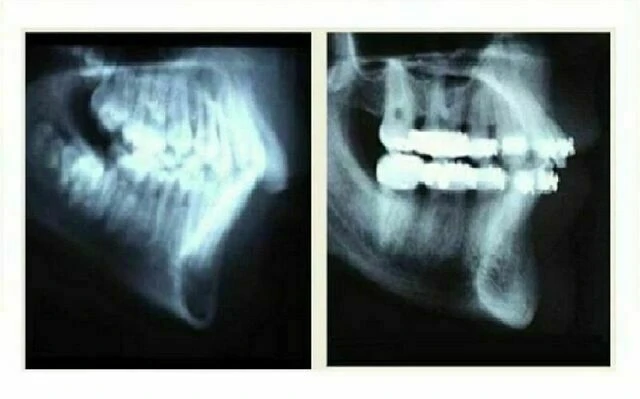

a. Phân tích phim sọ nghiêng:

Được sử dụng trong nhiều năm qua để xác định vị trí đúng của răng cửa dưới. Các phân tích Down, Holdaway, Ricketts…khuyến cáo xác định vị trí hàm dưới quanh đường APo để đạt được thẩm mỹ tối đa và duy trì ổn định. Phân tích Down thêm vào góc giữa răng cửa dưới với mặt phẳng hàm dưới, và Steiner dựa trên thông số của răng cửa dưới với đường NB. Tất cả những đo đạc đó đều là các giá trị dự đoán không đáng tin cậy cho sự vững ổn khi duy trì (theo nghiên cứu của trường đại học Washington). Thẩm mỹ khác nhau ở từng cá nhân, nhưng vị trí răng cửa dưới so với các đuờng có thể là đẹp với nha sĩ này nhưng lại là hô/chìa đối với nha sĩ khác.

Vài bác sỹ chỉnh nha được tin phải đặt vị trí răng cửa dưới “quá bản xương”. Có nghĩa là trục dọc của răng cửa dưới ở vùng symphysis hàm dưới sẽ quá nền xương.

Như ví dụ trên dây, răng cối nhỏ đã được nhổ và chân răng cửa ngả về phía lưỡi trong suốt quá trình kéo lùi răng, chạm vào xương vỏ phía trong. Răng không được coi là “quá bản xương”.